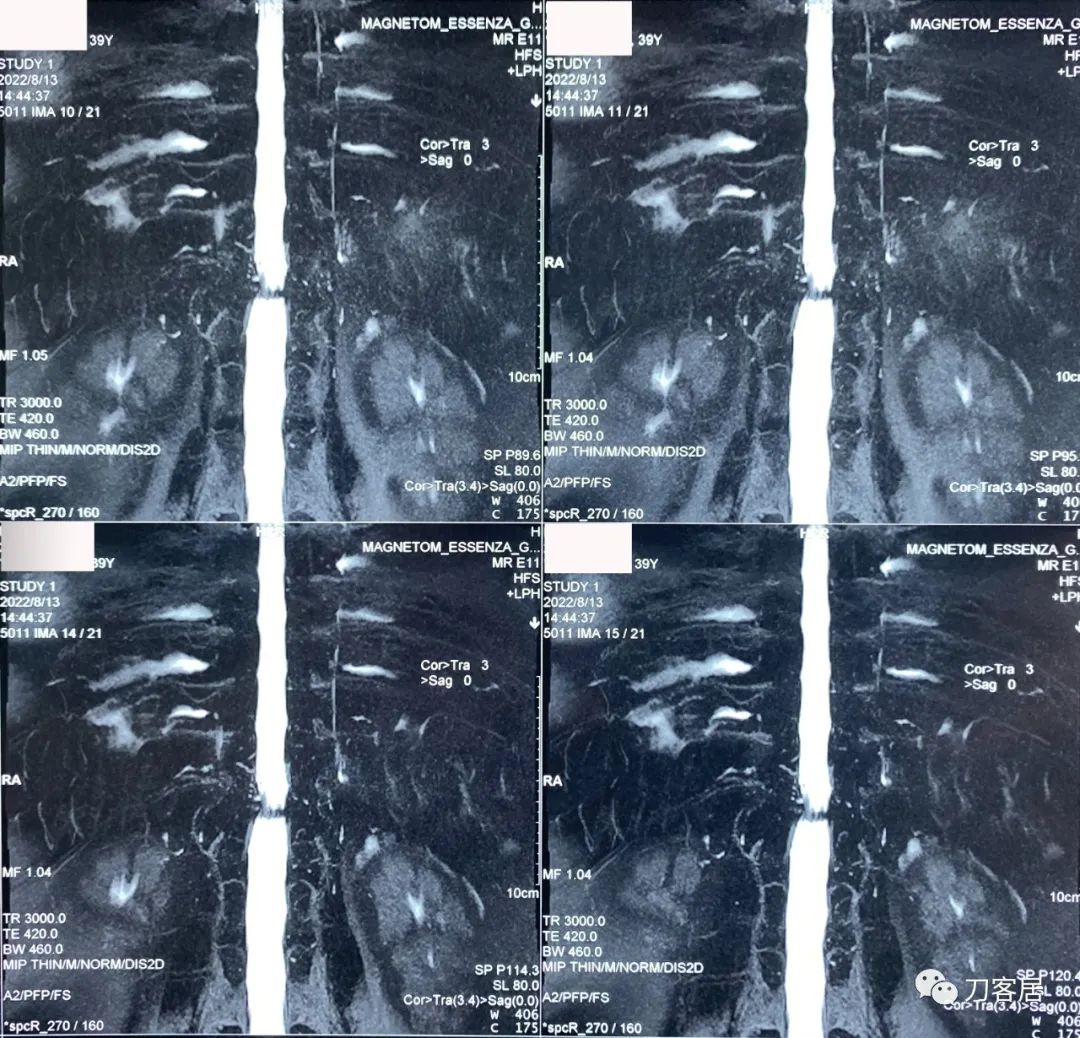

图9. 20220813西安第三方影像机构胸椎MRI03,脊髓水成像,显示胸11-12处脊髓受压。

图10. 20220813西安第三方影像机构胸椎MRI04,提示右侧隐窝狭窄,右侧黄韧带肥厚,但椎管狭窄并不那么严重。

图11. 20220813西安第三方影像机构胸椎MRI05,显示两侧胸椎黄韧带肥厚,右侧明显。但脊髓压迫似乎并不那么严重。

图12. 20220813西安第三方影像机构胸椎MRI06,显示两侧胸椎黄韧带肥厚,右侧明显。但脊髓压迫似乎并不那么严重。